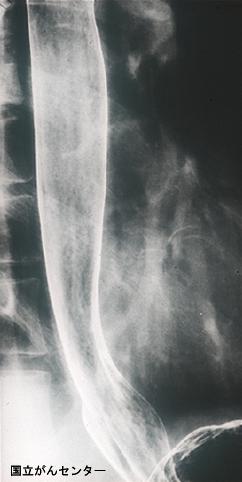

疾病(病理主体)的分类恶性上皮肿瘤/扁平上皮癌

部位(按器官分)食道/下

检查方法X线

肿瘤的肉眼分类0型(表在型)/IIc型(IIc)

肿瘤最大直径10~14

肿瘤的深度mm

多发性肿瘤(同一器官)有(同时性)